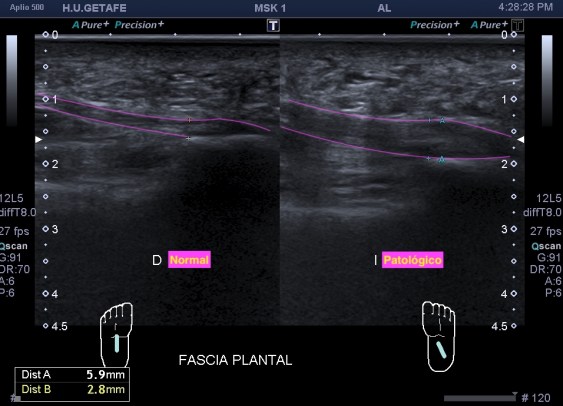

Este post es un compendio de todo lo que podemos encontrarnos, de manera habitual en la musculatura de la cara anterior del muslo, espero que disfrutes la lectura de este post, dividido en varias figuras patológicas con una rareza final que es la afectación de vasto intermedio…Buen domingo:

Lo único que me me llamó la atención fue la ecogenicidad (fig 1) de uno de los músculos del cuádriceps, en concreto el Recto Anterior, músculo anterior de la línea media de la musculatura en la cara anterior. Esta ecogenicidad era discretamente más ecogénica de lo habitual, sabemos que los músculos son hipoecogénicos por definición.

Inmediatamente exploré la misma zona del muslo contralateral, comprobando efectivamente los cambios en la ecogenicidad del músculo y cambios en el grosor, claramente disminuido en el lado afecto.